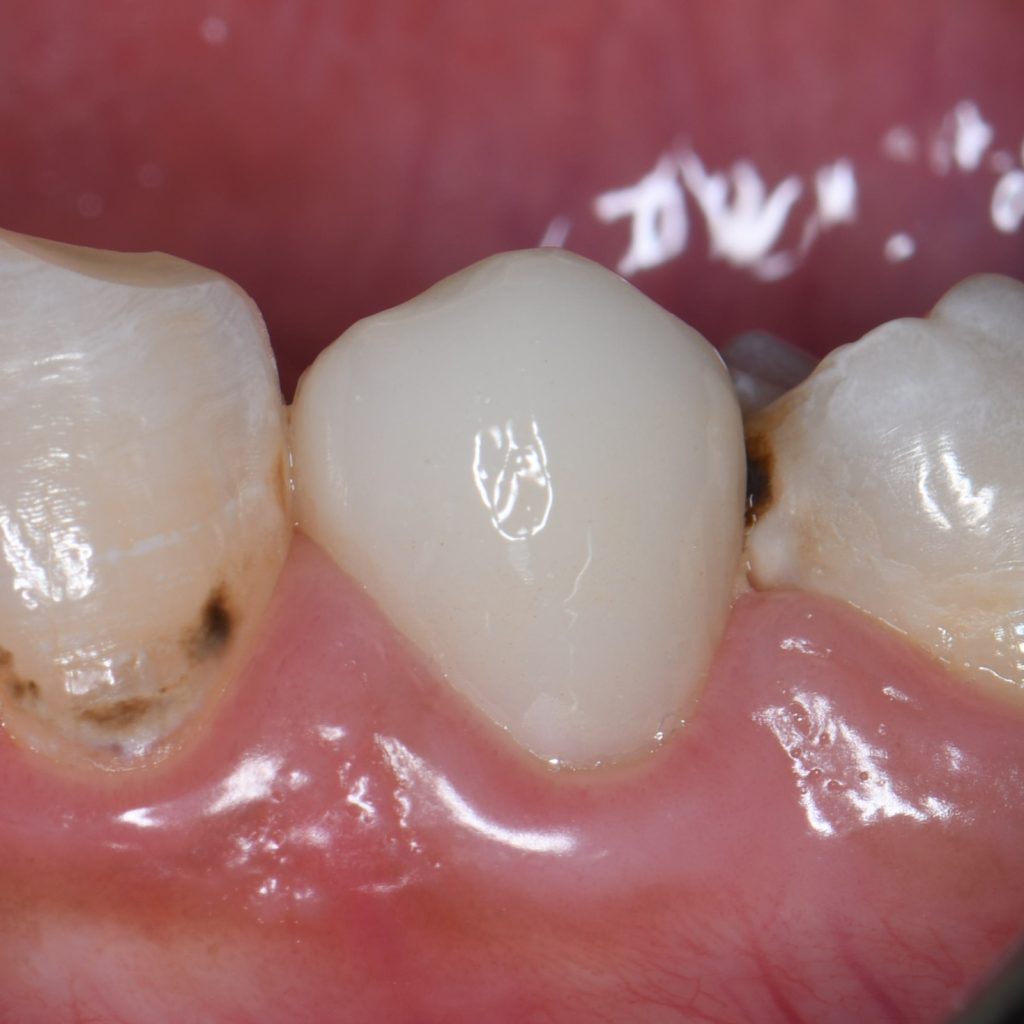

Follow up the case for more 1 year and still with good condition, aesthetic, functional and healthy

After gingiva healing

1 year follow up